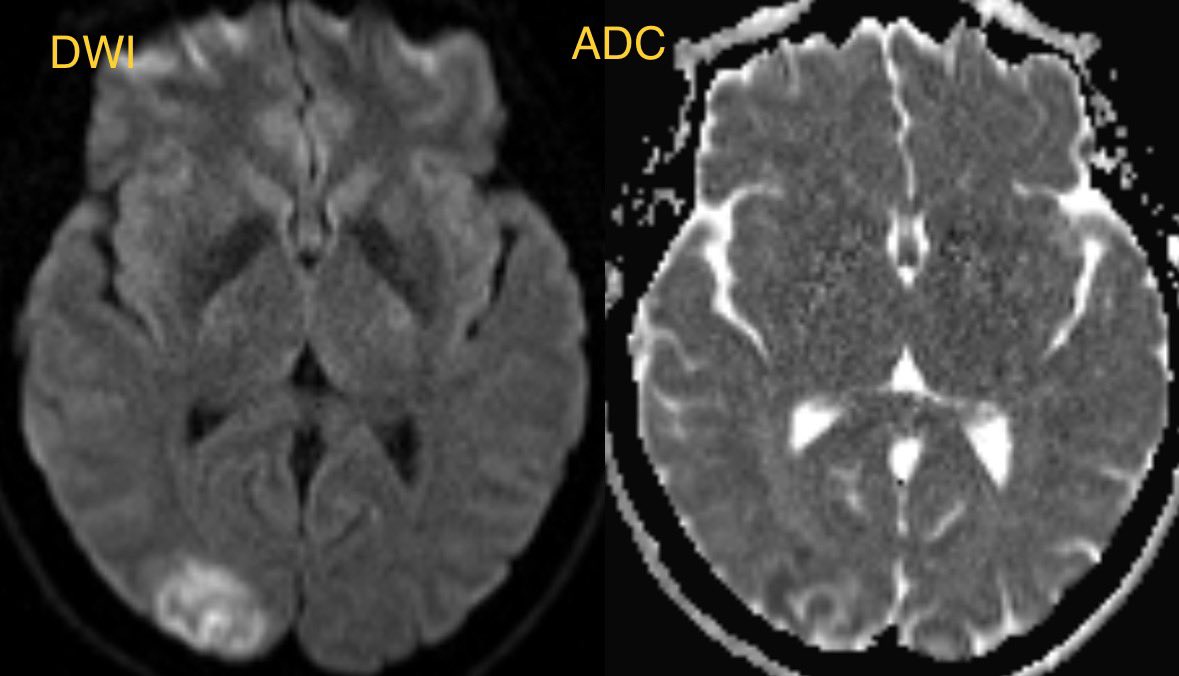

Initial MR shows cortical/subcortical restricted diffusion and edema predominantly in the right Occipital lobe

▶️convexity SAH, lobar hemorrhage, edema, and infarcts